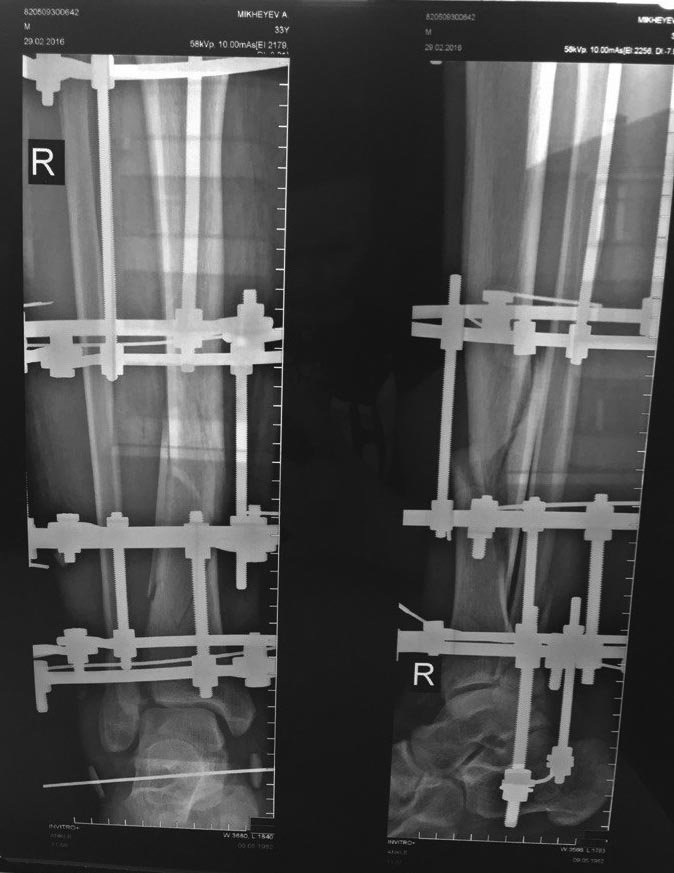

Закрытый спиральный перелом нижней трети обеих костей правой голени со смещением |

Добрый день! 28.01.2016 Был мной был получен данный диагноз по средствам катания с горок на лыжной базе. В этот же день в больнице просверлили пятку вставили спицу и положили на вытяжку. 2.02.2016 Была произведена операция и был установлен аппарат илизарова (т.К. Врачи сказали что перелом сложный и будет лучше с аппаратом чем с пластиной). 29.02.2016 Сделали рентген (снимок прилагается), снимок сделан как я понял с целью убрать самую первую спицу которая была сделана для вытяжки и которая фиксирует в одном положении. Собираюсь с этим снимком теперь к врачу. Но судя по снимку что то ничего не изменилось или так и должно быть ? Ногой потихоньку двигаю лежа(поднимаю, сгибаю) ну и на костылях немножко прыгаю. Подскажите пожалуйста есть ли какие либо улучшения или наоборот ? А то что то тревожно стало когда сегодня снимок посмотрел а там на мой взгляд все без изменений. Заранее благодарен.